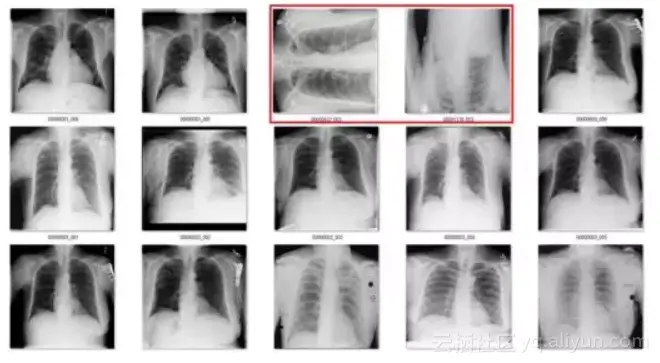

在医学成像中,数据存储档案是基于临床假设的。不幸的是,这意味着当你想要提取一个图像时,比如一个正面的胸部x光片,你通常会获得一个存储了许多其他图像的文件夹,并且没有简单的方法来对它们加以区分。

图1:这些图片来自于相同的文件夹是有道理的,因为在放射学中我们记录的是病例而非图像。这是病人受伤后,同时扫描的所有身体部位。